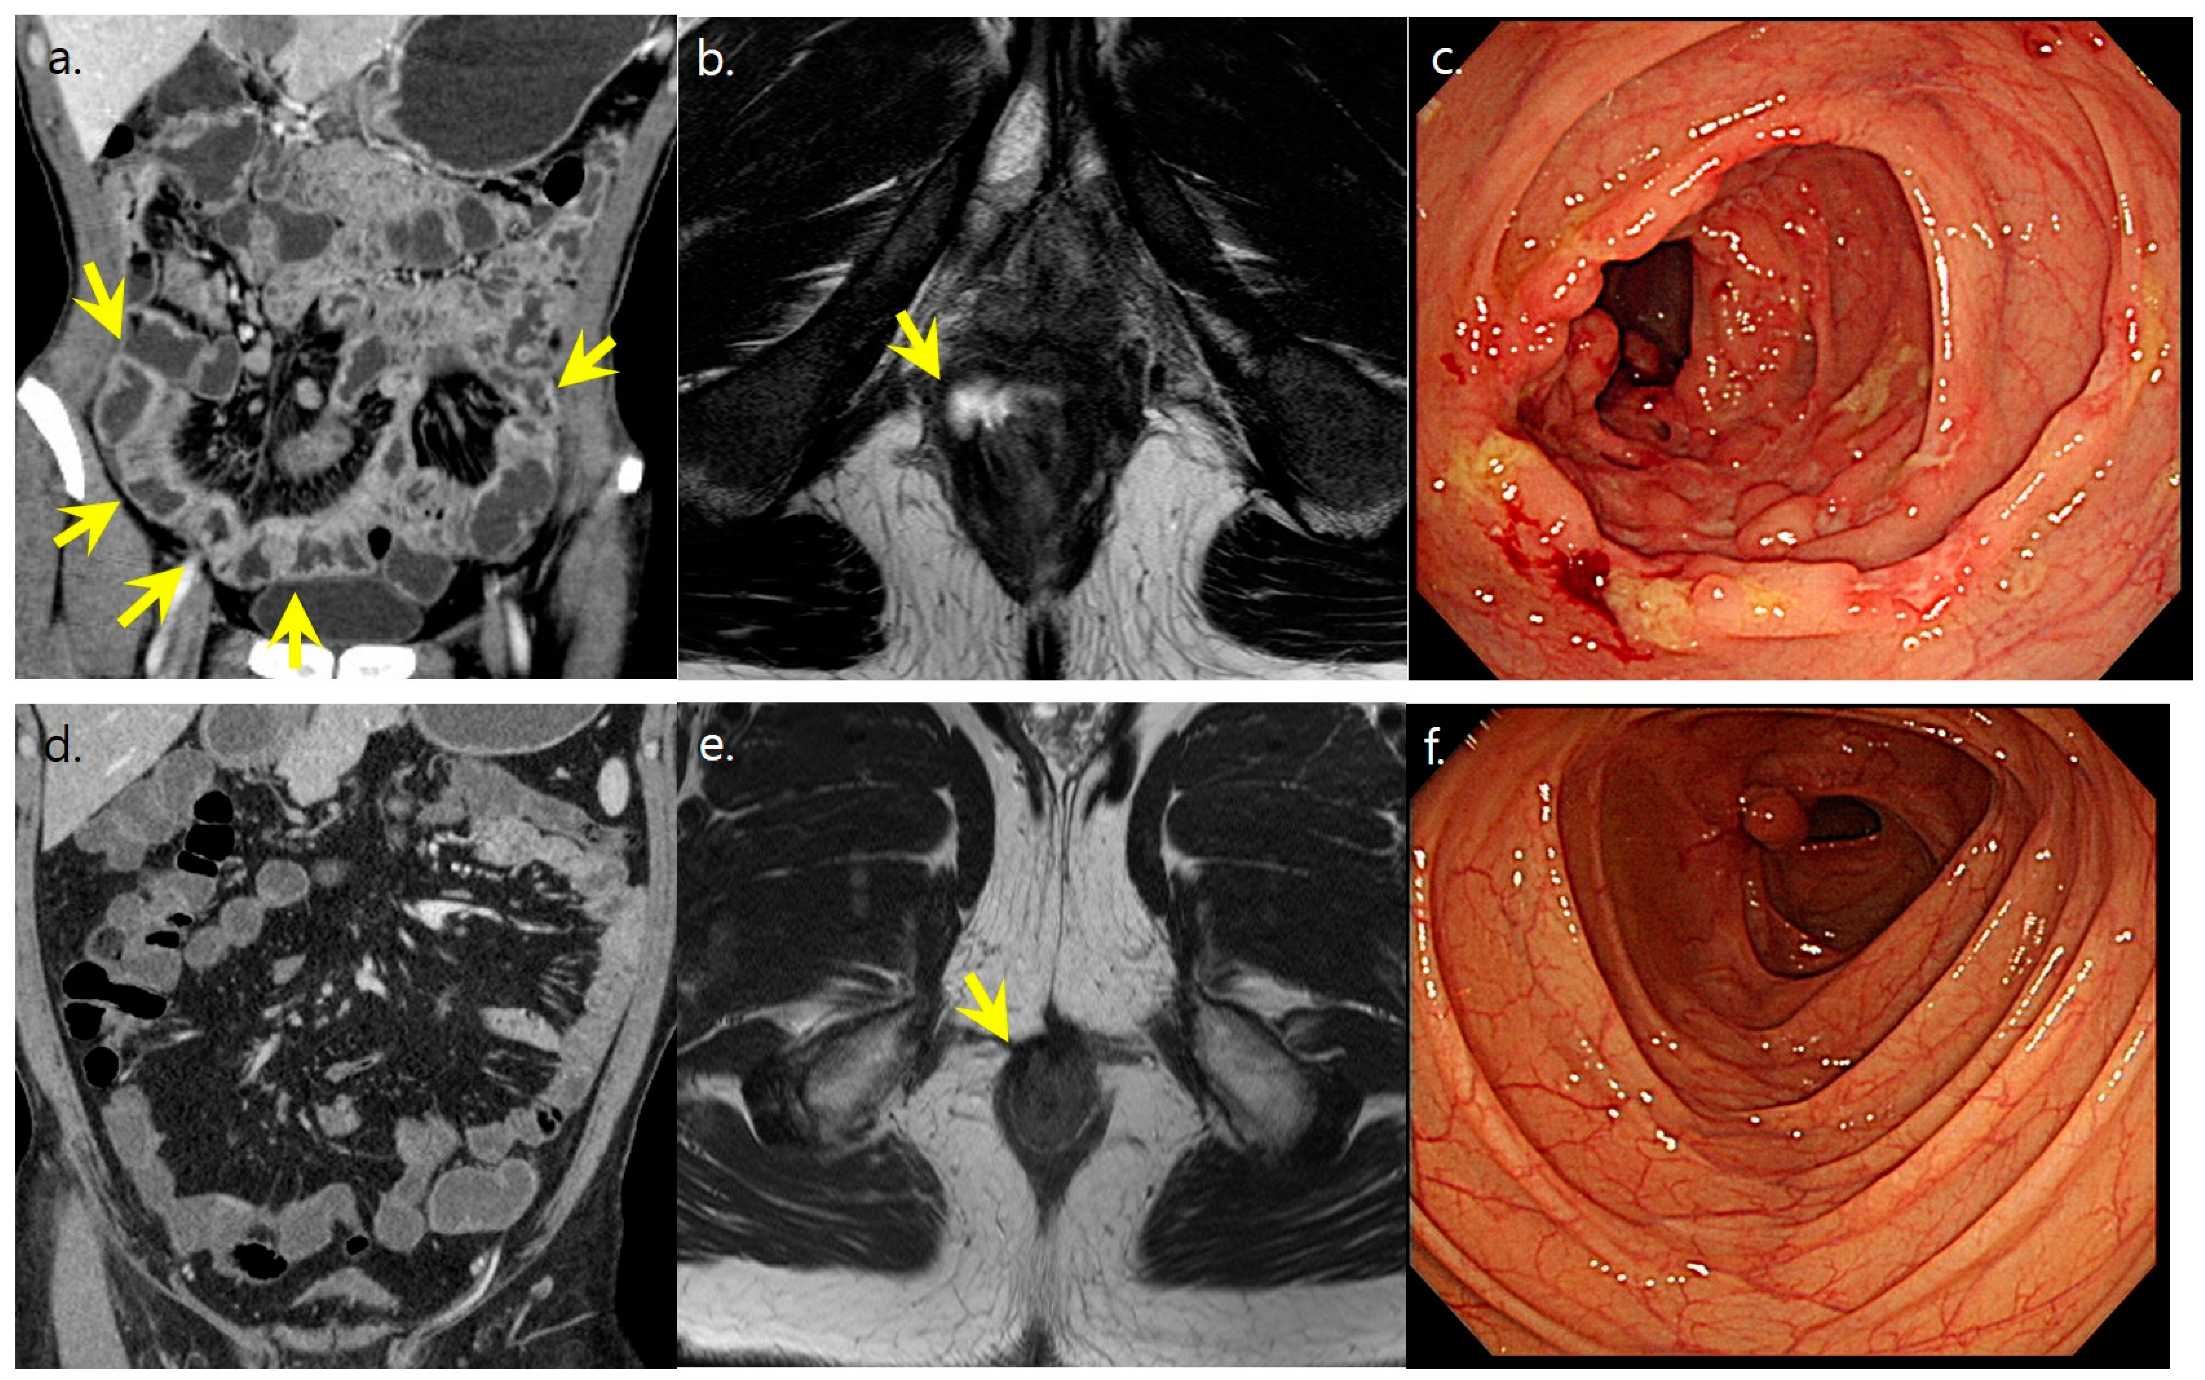

2.3. Radiologic and Endoscopic Analyses of Disease Pattern